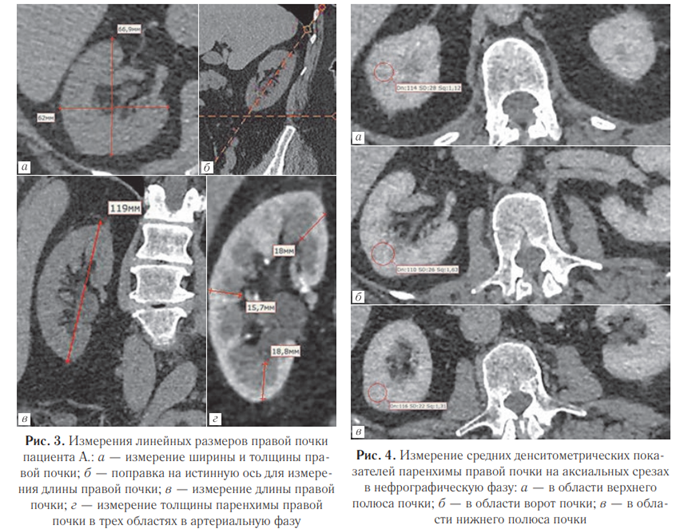

Методика определения объема почек на основе измерения их линейных размеров. При отсутствии возможности произвести расчет раздельной функции почек с помощью специализированного программного обеспечения была разработана альтернативная методика оценки раздельной функции почек при помощи КТ, основанная на ручных измерениях объема почечной паренхимы (по ее линейным размерам) и ее денситометрических показателей.

Для измерения объема были определены наиболее используемые в клинической практике линейные размеры почек:

— два перпендикулярных друг другу размера на аксиальном срезе — ширина паренхимы и толщина паренхимы (рис. 3, а);

— одно наибольшее измерение почки на фронтальном срезе с поправкой на истинную ось органа — длина почки (рис. 3, б, в);

— три измерения толщины паренхимы на фронтальном срезе в области верхнего и нижнего полюсов и в середине почечной паренхимы (рис. 3, г).

В дальнейшем полученные данные использовались для разработки формулы расчета объема паренхимы почки с помощью регрессионного анализа на основе промежуточной выборки пациентов, состоящей из 120 человек.

Полученная формула для определения объема паренхимы, учитывающая шесть линейных размеров (ширина и толщина на аксиальном срезе; длина на фронтальном срезе; среднее арифметическое трех измерений толщины паренхимы на фронтальном срезе), показала высокую точность. Корреляция (0,994, p<0,001) и ковариация (0,94, p<0,001 между объемами, рассчитанными по формуле, и объемами, полученными при автоматической сегментации, подтверждают адекватность модели. Эта формула успешно преодолевает основной недостаток классического эллипсоидного метода за счет исключения объема синуса почки из общего объема почечной паренхимы. Хотя метод требует больше измерений, чем простой эллипсоидный, он существенно менее трудоемок, чем ручная послойная сегментация или предложенные в предшествующих работах формулы, и обеспечивает высокую точность при отсутствии автоматизированных инструментов.

2. Точность измерений: субъективность при определении точек замера линейных параметров почки потенциально влияет на точность. Для минимизации погрешности, особенно при измерении толщины паренхимы, рекомендуется использовать артериальную фазу контрастирования, обеспечивающую четкую визуализацию почечных столбов и соответствие методике настоящего исследования. В отсутствие артериальной фазы допустимы измерения по нативным сканам или в нефрографическую фазу.